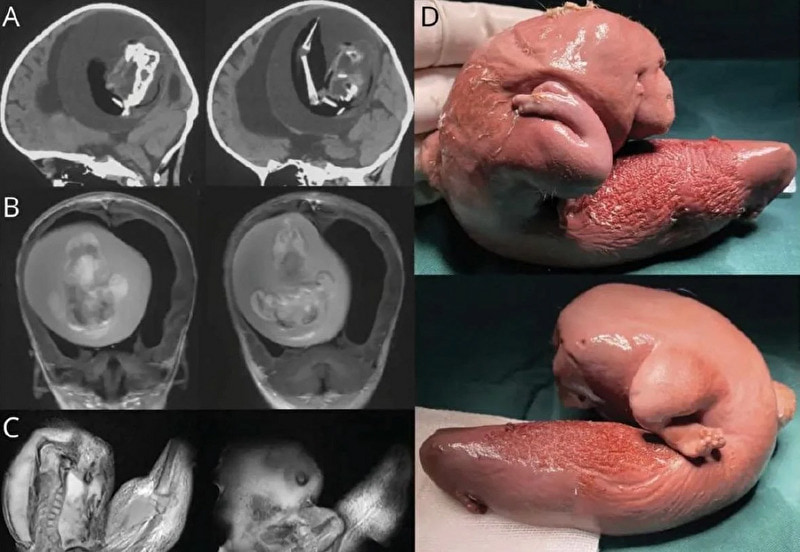

gif_animation (※ TOP画は完全にイメージ)ですが、海外にてとある幼女の体内から取り出された「赤ちゃん(胎児)」の姿があまりにもヤバイ…画像。それは1歳の女の子の脳内から摘出されたもので、消失した双子の胎児の一部がもう1人の胎児の中に宿る「寄生性双胎児」と言われる症例。その確率は50万人に1人と言われている。

※ 画像